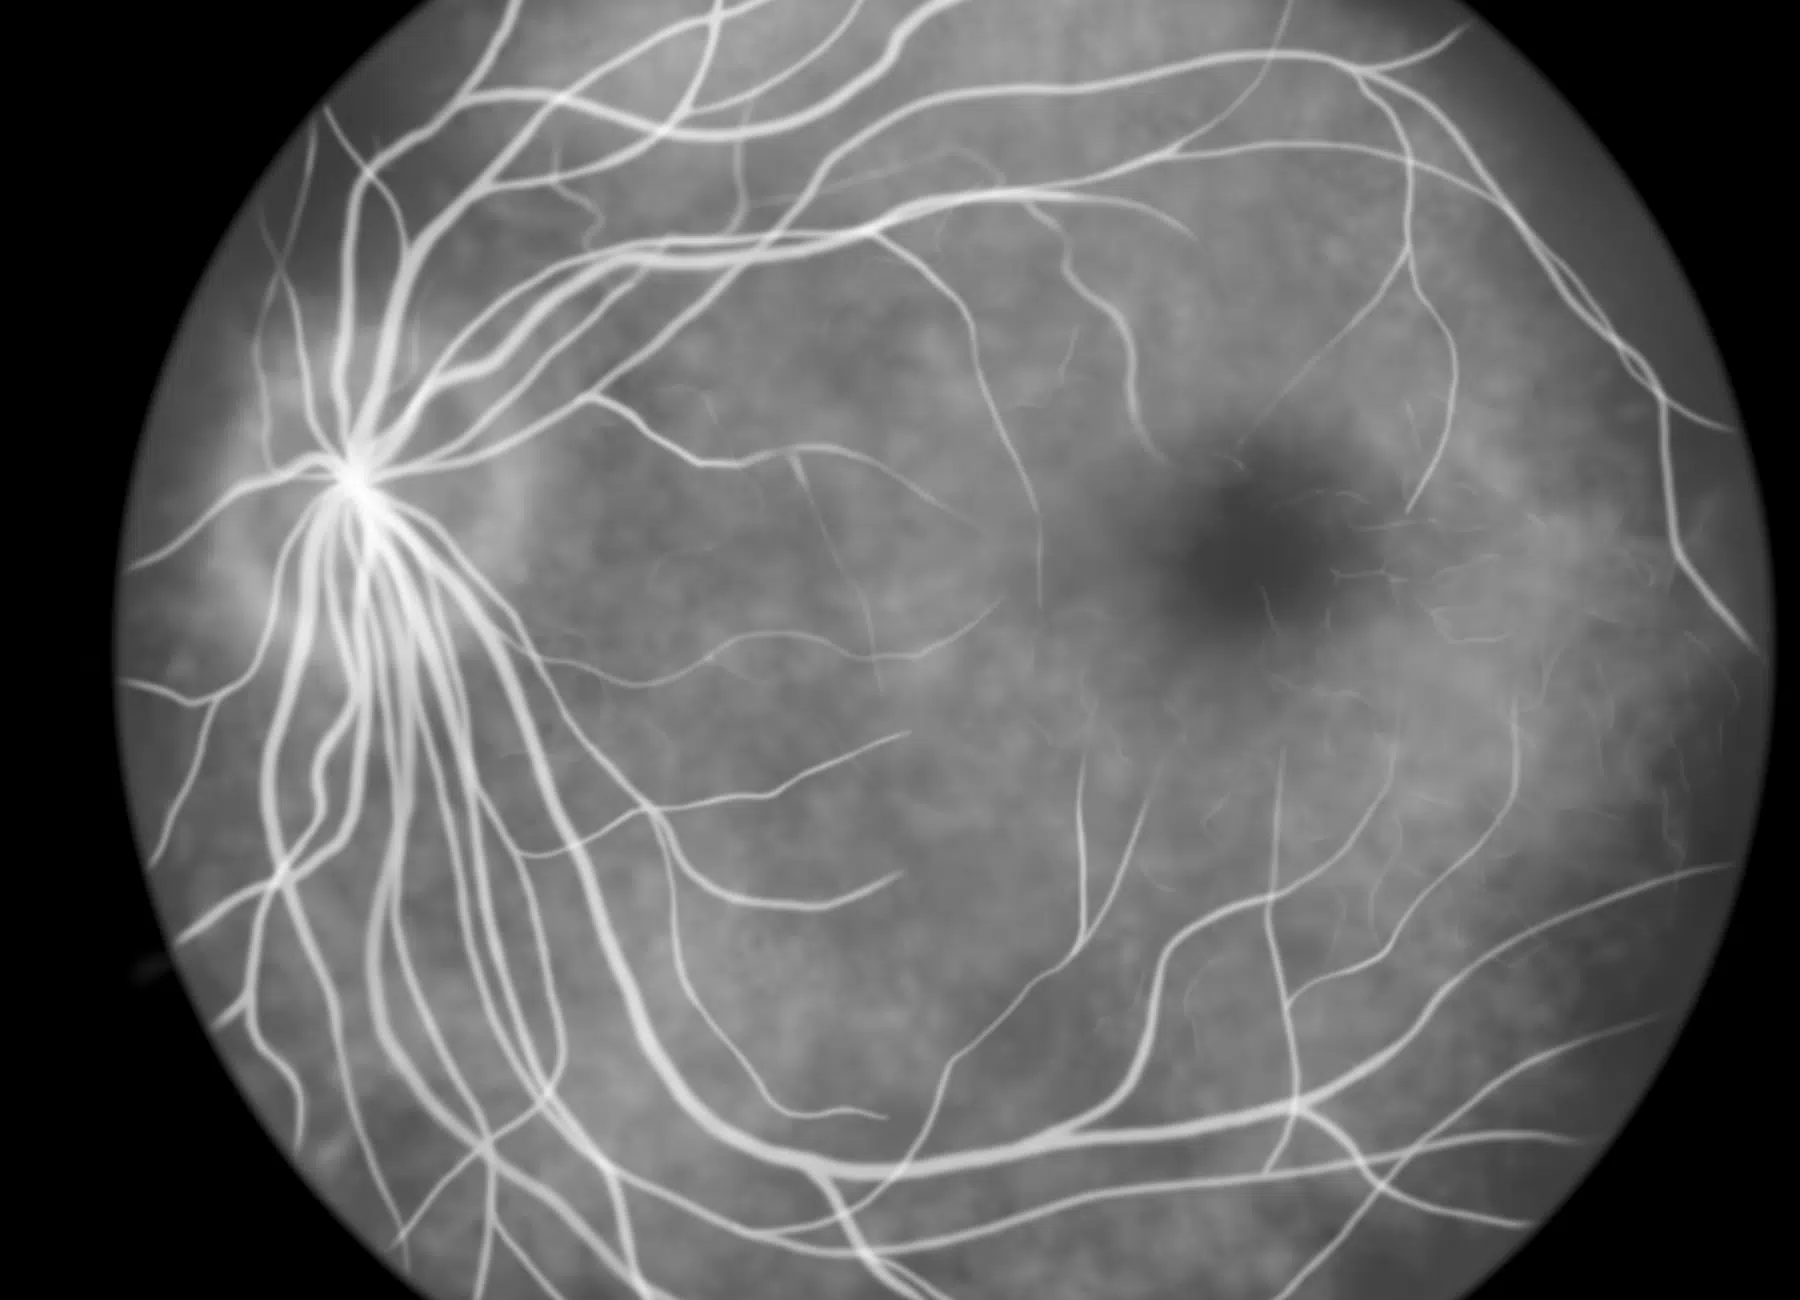

L’angiographie par injection de produit de contraste est indiquée lorsqu’une évaluation plus poussée est nécessaire pour confirmer un diagnostic ou détecter des anomalies vasculaires rétiniennes non visibles via l’OCT-A. Elle est particulièrement utile dans certaines situations cliniques spécifiques.

Elle permet notamment d’identifier des fuites de vaisseaux sanguins, comme celles observées dans les formes exsudatives de DMLA, où elle aide à évaluer l’activité de la maladie et à ajuster les traitements en conséquence. Elle est également précieuse pour le suivi des atteintes rétiniennes liées à des pathologies systémiques telles que les maladies inflammatoires, les rétinopathies hypertensives ou certaines infections affectant les vaisseaux de la rétine.

En présence de tumeurs rétiniennes, cette technique permet d’analyser la vascularisation tumorale et d’évaluer les réseaux vasculaires anormaux associés à des lésions néoplasiques. Elle est aussi indiquée après une intervention chirurgicale ou un traitement au laser, afin d’observer la réponse vasculaire post-thérapeutique.

Bien que l’OCT-A soit appréciée pour son caractère non invasif et sa capacité à permettre un suivi régulier, l’angiographie par injection reste incontournable lorsqu’une visualisation fine et détaillée des structures vasculaires est requise. Ces deux méthodes se complètent parfaitement pour une prise en charge ophtalmologique précise et personnalisée.